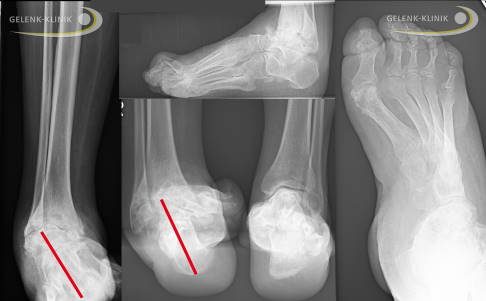

Fehlstellung des Fersenbeins

Im Rahmen der Charcot-Marie-Tooth-Erkrankung tritt auch eine Standunsicherheit auf. Diese ist abhängig von der Fehlstellung der Ferse. Die Ferse steht durch die normale Funktion der Wade und der innen liegenden Beugesehnen und hinteren Schienbeinsehne bei einer Schwächung der äußeren und vorne liegenden Sehnen nach innen gekippt (Varusstellung). Diese Verkippung führt vermehrt zum Umknicken des Fußes. Die Standbasis-Fläche wird durch die Belastung auf dem Außenrand geringer. Dies reduziert die Beweglichkeit im oberen Sprunggelenk. Ursächlich sind die veränderten Zugverhältnisse, aber auch ein knöcherner Anschlag (Impingement) am vorderen Sprunggelenk durch die veränderte Fußform. Die Veränderungen sind durch die Schädigung der motorischen Nerven erklärbar.

Fehlstellungen des Rückfußes

Die Charcot-Marie-Tooth-Erkrankung wirkt sich nicht nur auf den Fuß und auf die Zehen aus, sondern auch auf den Rückfuß. Die Auswirkungen auf den Rückfuß durch die veränderten Muskelzüge können teilweise gut kompensiert werden. Zum Teil entstehen durch die resultierende Fehlstellung – häufig in Kombination mit Verletzungen der Bänder – weitreichende Schädigungen des Sprunggelenkes. Die Fehlstellung wirkt sich dann auch auf das gesamte Bein aus. So können X-Beinachsen entstehen. Durch die Fehlstellung des Fußes resultiert häufig auch eine veränderte Rotation im Unterschenkel. Diese Auswirkungen können individuell sehr verschieden sein. Sie hängen sehr stark vom individuellen Befallsmuster ab. Die Prinzipien sind bei allen Patienten mit CMT-Erkrankungen ähnlich, aber nie gleich.

Therapieprinzip bei Fehlstellung des Fußlängsgewölbes

Im Hinblick auf eine aus der langjährigen Fehlstellung des Hohlfußes häufig resultierende Arthrose des Sprunggelenkes können weitere Operationen sinnvoll sein. Eine Begradigung von Schrägstellungen steht bei diesen Methoden immer im Vordergrund. Schiefe Achsen sind, wenn symptomatische Arthrosen vorhanden sind, immer ein Grund für eine Korrektur. Diese ermöglichen häufig eine kausale (ursächliche) Therapie und eine vorübergehende Besserung der Sprunggelenksarthrose. Leider sind Arthrosen, die einmal entstanden sind, nicht mehr zu heilen. Sie schreiten aber nach solchen Maßnahmen oft langsamer fort.

Sinnvoll sind solche Operationen vor allem bei beginnender Arthrose mit Fehlstellung, damit im Verlauf keine Versteifung (Arthrodese) oder Sprunggelenksprothese notwendig wird. Leider wird insbesondere am Fuß und Sprunggelenk diese Chance oft leichtfertig vertan, da häufig keine andere Therapieoption außer Versteifen bekannt ist.